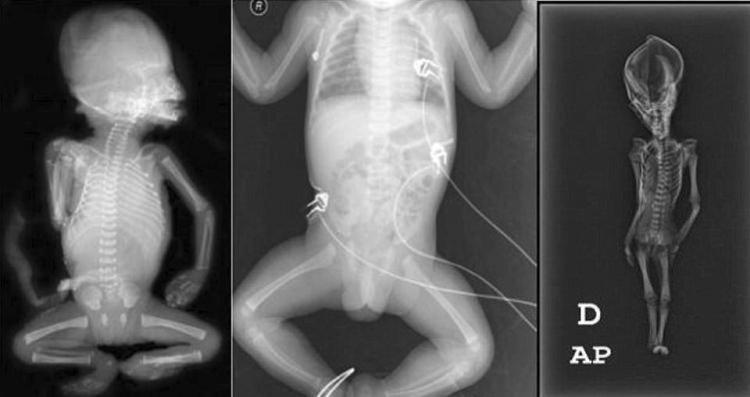

Geçtiğimiz aylarda yapılan bir başka araştırma ortaya daha farklı sonuçlar koymuştu.

California Üniversitesi, San Francisco Üniversitesi ve Stanford Üniversitesi tarafından “Ata” ismi verilen mumyaya yapılan DNA analizleri, ,gizemini uzun süre koruyan kalıntının, çeşitli genetik mutasyonlara uğramış, 6-8 yaşında olduğu tahmin tahmin edilen cüce bir kız çocuğuna ait olduğunu ortaya koymuştu.

Yapılan bilimsel çalışmalar, çocuğun 40 yıl önce öldüğünü ve bugüne kadar tanımlanmamış olan gen bozukluklarına sahip olduğunu açığa çıkarmıştı.